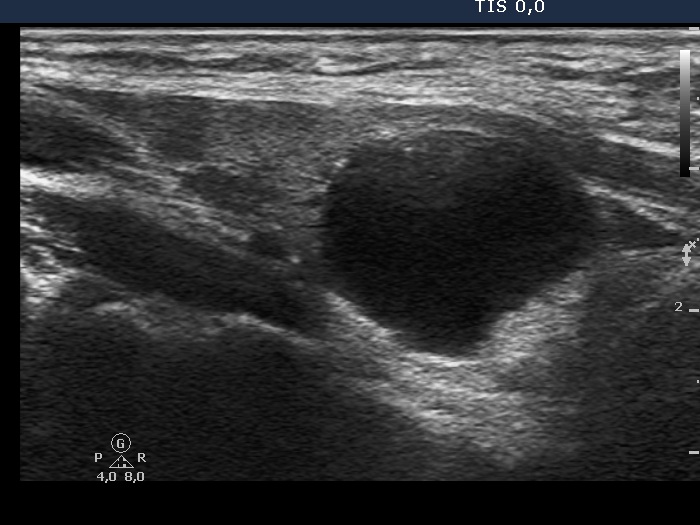

Second examination 2 years later (2nd row of images)

Clinical presentation. The patient had no complaints.

Palpation: no abnormality.

Ultrasonography. The pattern was essentially the same. The cyst has recurred.

1.8 mL watery fluid was aspirated.

Suggestion: ultrasound examination every second year.

Comment. The watery color of the cystic fluid is very specific for parathyroid origin.